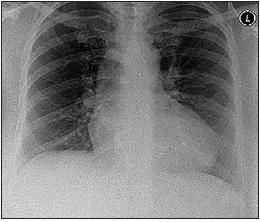

A chest radiograph obtained 5 weeks later showed complete resolution of the effusion (Figure 4).

Figure 4 – This chest radiograph obtained 5 weeks after excision of the patient's ovarian tumor shows resolution of the pleural effusion.